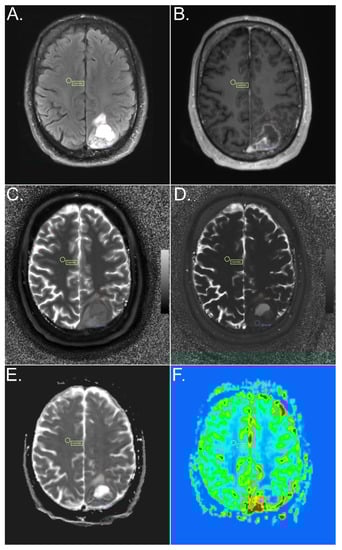

2.3. Region-of-Interest (ROI) Evaluation